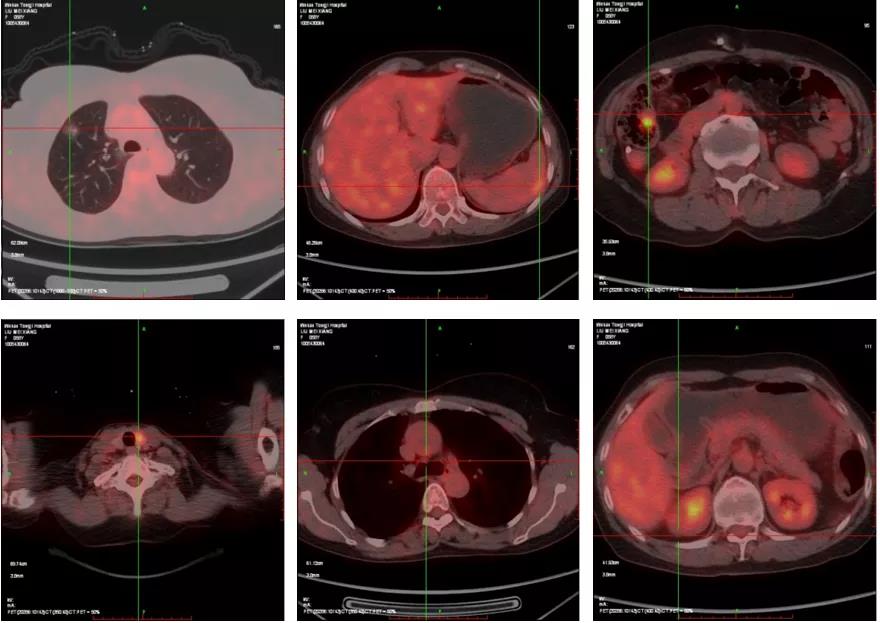

2017年12月,患者复查CA-125 55.0 U/ml,余未诉不适。PET-CT:1.右肺上叶磨玻璃影,部分代谢轻度增高,考虑为肿瘤性病变可能。2.脾脏包膜下局部片状代谢增高影,不除外转移性肿瘤可能。3.升结肠局部壁厚,代谢增高,不除外肿瘤性病变。4.双侧颈部、纵膈及右侧膈肌脚后淋巴结增多,部分稍大,部分代谢增高,考虑卵巢癌复发(图2)。综合考虑,患者为临床复发。

图2 患者第一次临床复发PET-CT结果